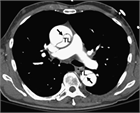

1. 急性の上背部痛の患者では、胸痛患者と同様の「致死的な胸痛疾患」を常に疑う必要がある。すなわち、急性心筋梗塞、急性大動脈解離、緊張性気胸、肺塞栓症である(推奨度1)

1. 急性大動脈解離は、突然の背部痛(感度84%)のほかに、裂ける痛み、移動する痛みがある場合に疑う(推奨度1)